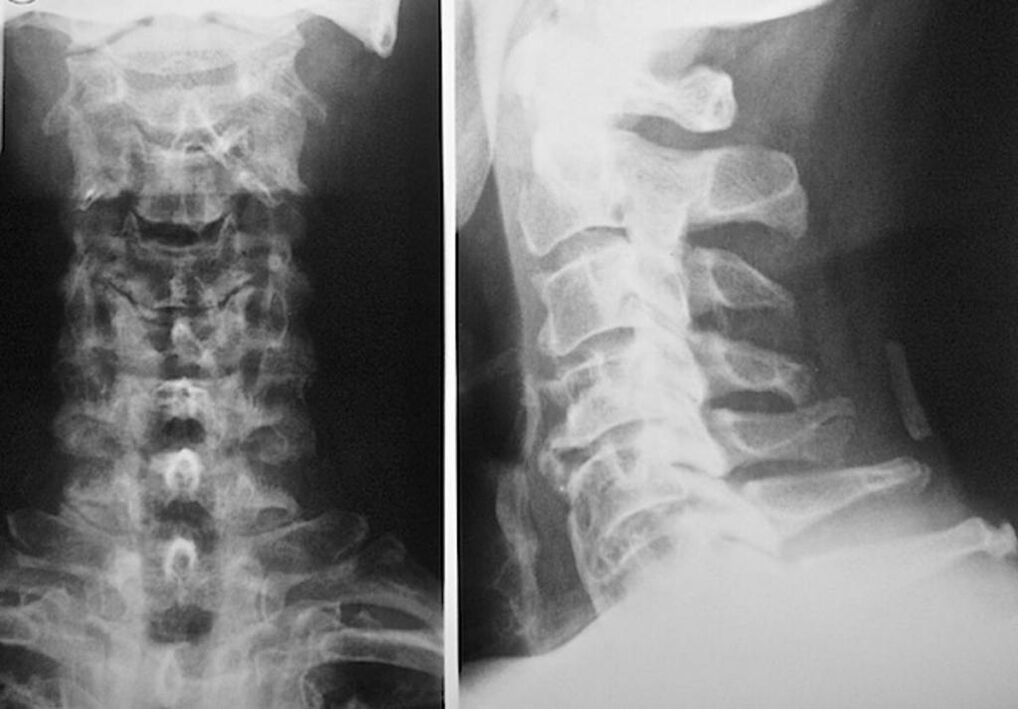

The following research methods are used to accurately diagnose and assess the condition of intervertebral discs:

- Radiography.

- CT scan.

- Magnetic tomography.

- Ultrasound scan of the neck vessels.

Each of them is completely safe for health and does not carry any threat of excessive exposure. The diagnosis of osteochondrosis of the cervical vertebrae, the treatment of which will be carried out throughout the rest of life, can be made after a simple visual examination. Any orthopedist can do this easily. The exception is the first stage of the disease, when no obvious pathologies of the cervical region are observed.